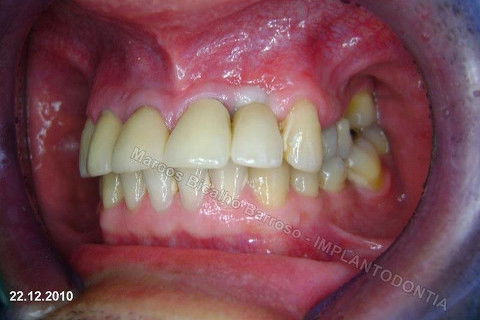

Este caso tem o objetivo de demonstração da técnica que normalmente sigo ; em casos onde ocorre fratura da raiz e consequentemente abscessos, com ou sem formação de fístula. Neste caso fiz a exodontia com preenchimento do alvéolo com biomaterial (osso bovino liofilizado + coágulo do paciente). Após 90 dias, mais ou menos, instalei o implante. Esperei mais 4 meses e realizei ontem (12/11/2010) a instalação do cicatrizador com o cuidado de preservar tecido mole, sem remoção de material, apenas afastando gengiva e "enrolando" a sobra de mucosa em direção a face vestibular, para promover conservação de papila futuramente. Se ocorrer excesso de papila, sem problema, remove-se um pouco, mas a intenção é não deixar faltar, o que resultaria em indicação para enxertos gengivais.